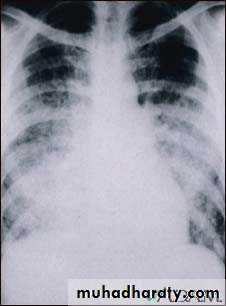

Chickenpox pulmonary x-ray

Varicella (Chickenpox)Bacterial superinfection

Varicella pneumonia